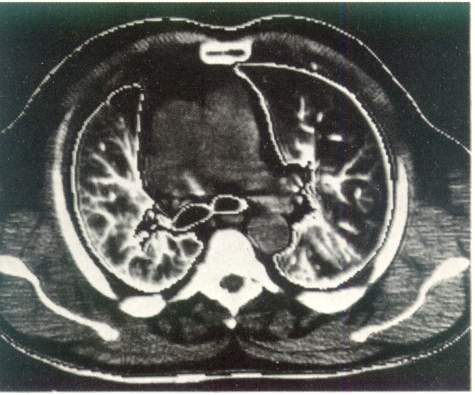

Возможности рентгенологической диагностики заметно расширились за счет становления и клинического использования компьютерной рентгенотомографии

. По сравнению с обычной рентгенографией компьютерная рентгенография имеет в десятки раз большую разрешающую способность и позволяет различать ткани с разностью по плотности до 0,5 %.

Это дает возможность четко определять границу между нормальной и патологически измененной легочной тканью. На компьютерных томограммах

органов грудной полости удается не только локализовать патологический очаг, но и определить его размеры, оценить плотность и однородность, соотношение с соседними анатомическими образованиями и органами.

Рис. 3.

Компьютерная томография органов грудной клетки. Норма.

Компьютерная томография дает возможность получить наиболее полную рентгенологическую информацию об опухолях и кистах средостения, сосудистых изменениях в легких, аневризмах, о состоянии трахеобронхиального

дерева, характере и структуре «шаровидных образований в легких», патологических изменениях в плевре, грудной стенке, особенно при ее злокачественных поражениях (рис. 3).